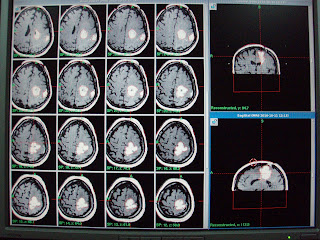

On referral, for She had presented progressive recurrence of right hemiparesis and fits since first week of April 2010. On Clinical examination, she had House Brackmann right facial palsy grade I-II and right hemiplegia. MRI brain with contrast had revealed multiple heterogeneous rim enhancing mass in the left parietal region with significant perilesional edema. Patient referred us for management with GKSRS. Risk of GKSRS explained. These agreed upon wished to proceed. She had treatment with following prescription.

Multiple isocenters with 18 & 8 mm collimator used in APS mode. She discharged on tapering doses of Dexamethasone and advised follow up after 3 months.